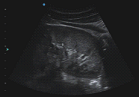

⦁ Abdomen

⦁ Urología

⦁ Ginecología

⦁ Obstetricia (1er Trimestre, 2do y 3er Trimestre)

⦁ Eco fetal

⦁ Embarazos gemelares